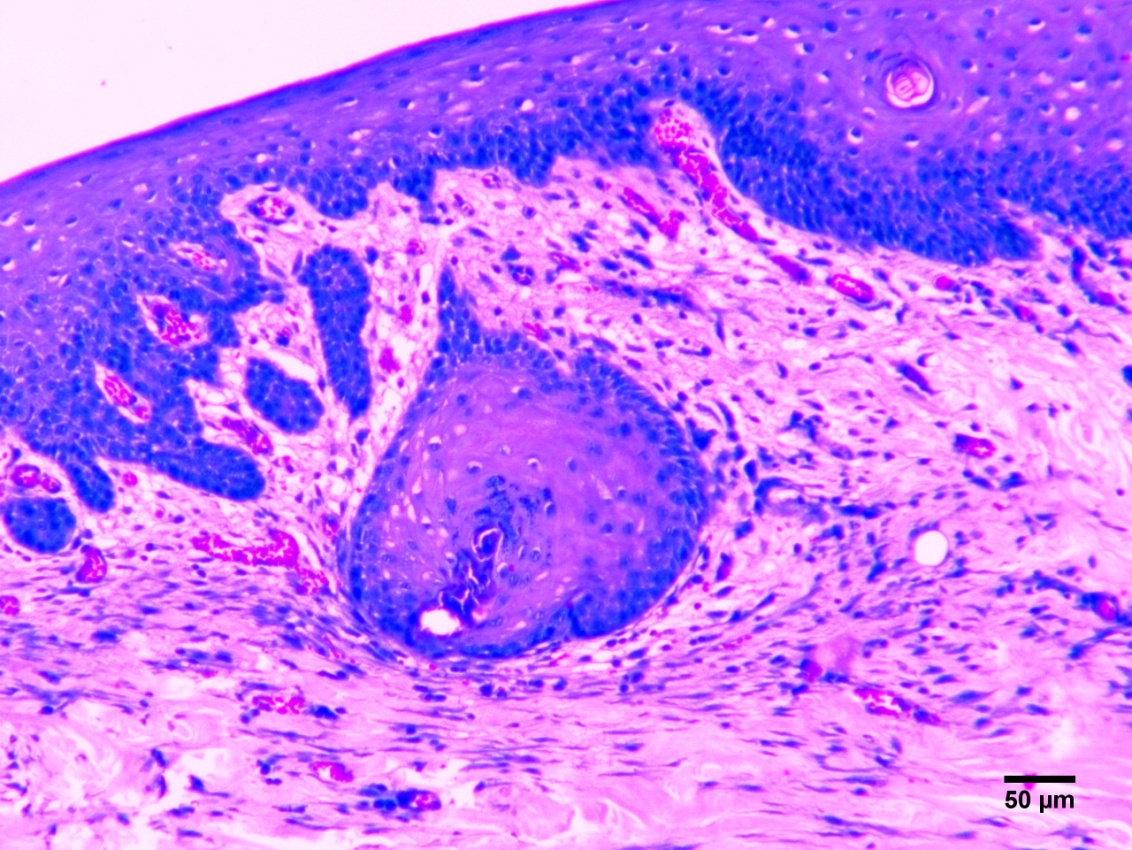

O presente estudo teve por objetivo desenvolver e investigar experimentalmente as potencialidades de aplicação de bioadesivo a base de amido aditivado, como sistema patches transdérmico e intradérmico epitelial, em formato de filme monolaminar tubular, visando à ação futura para administração de anti-inflamatórios, antimicrobianos e atuação terapêutica. Foram utilizados 20 coelhos machos e fêmeas, da raça Nova Zelândia, adultos, separados em quatro grupos com cinco animais que passaram por cirurgia para realização de defeito dérmico. O grupo GA e o grupo GB (controle dérmico e intradérmico negativos respectivamente) não receberam biomaterial na ferida. Os animais do grupo GC receberam o biofilme adesivo de forma dérmica que foi suturado sobre a ferida e o grupo GD, recebeu o biofilme adesivo de forma intradérmica. Aos sete e 14 dias de pós-operatório os animais foram anestesiados novamente para criação do defeito para biópsia. A análise estatística da planimetria foi conduzida a partir da média dos grupos, utilizando-se o teste de Tukey a significância de 1%, através do software computacional estatístico SAS®. A pesquisa demonstrou que o biofilme utilizado até sete dias reduz o processo inflamatório e estimula a neoangiogênse.